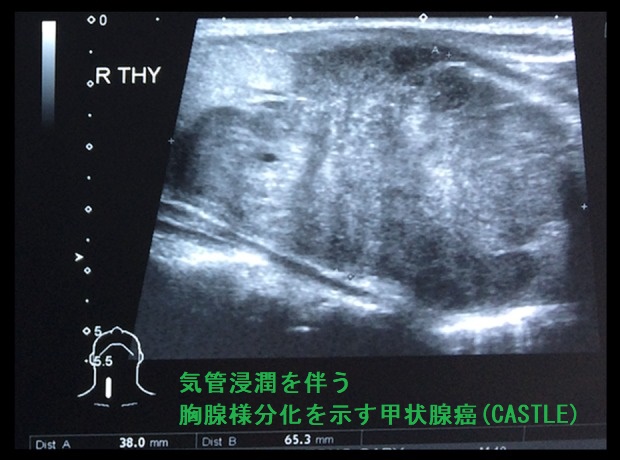

- 気管浸潤を伴うケースもある[Am J Case Rep. 2019 Dec 10;20:1845-1851.]

甲状腺の胸腺様分化を示す癌(CASTLE)の超音波(エコー)画像は、甲状腺悪性リンパ腫、甲状腺未分化癌、甲状腺原発扁平上皮癌と鑑別難で、辺縁不整・境界不明瞭、内部は不均一の低エコー結節(あるいは領域)。[Oncol Lett. 2016 Feb;11(2):1321-1326.]